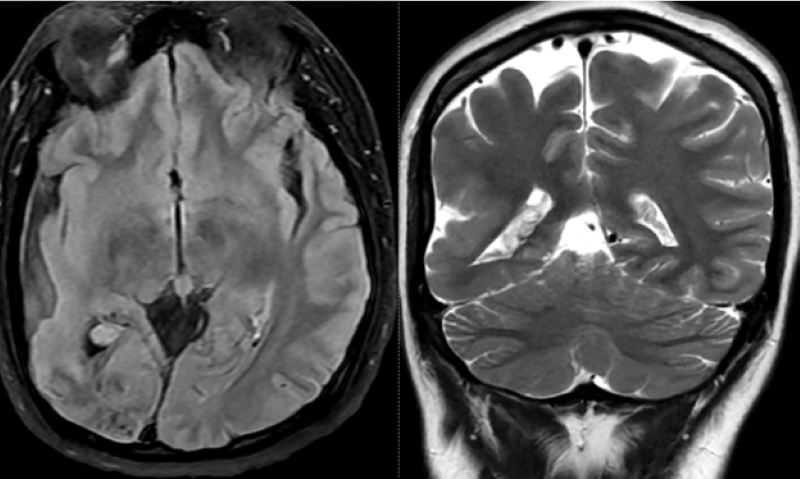

Đáng chú ý, trên phim chụp MRI sọ não phát hiện hình ảnh đám tổn thương cũ có vôi hóa, teo não thùy chẩm phải (vùng xuất phát của tia thị giác). Phì đại đám rối mạch mạc trong não thất bên phải. Thiểu sản động mạch đốt sống bên phải đoạn nội sọ.

Bất thường được phát hiện trên phim chụp MRI sọ não/Ảnh Medlatec